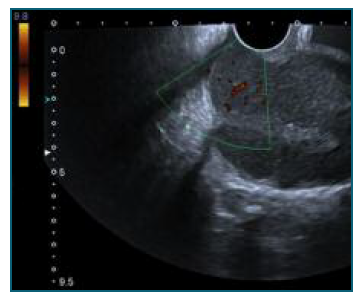

76 years old, obstetric index 3003, menopause at 58 years old, with history of arterial hypertension, obesity, type 2 diabetes mellitus, dyslipidemia, and pacemaker. She was admitted to the emergency department with complaints of vaginal bleeding since the previous day but was otherwise asymptomatic. Physical examination revealed the presence of abundant clots in the vagina and a very widened cervix was identified. It was not possible to visualize the external cervical os. On bimanual examination, the cervix was very hardened and enlarged. Transvaginal ultrasound showed a heterogeneous uterus, in an indifferent position, measuring 132x67x64 mm, an uterine cervix 49 mm long, widened and highly vascularized, and an endometrial thickening of 11 mm (Figure 1). An uterine curettage was performed and the material was sent for anatomopathological study. The histological examination revealed a non-Hodgkin B lymphoma, CD20+, whose morphology and immunohistochemical profile were compatible with a grade 1-2 follicular lymphoma with low ki67 proliferative index (15%). The patient was referred for a hematology oncology appointment. The additional investigation, which included a thoraco-abdominopelvic CT and positron emitting tomography (PET), showed a large heterogeneous lesion in the cervix with extension to the uterine body, multiple infradiaphragmatic adenopathies and subcutaneous/musculoskeletal and osteomedullary involvement, corresponding to a stage IV-A lymphoma (Ann Arbor classification). After 8 cycles of therapy with rituximab, cyclophosphamide, vincristine, and prednisone (R-CVP), a new PET scan was performed, which showed a complete metabolic response to therapy. The patient will start a 2 year maintenance immuno-chemotherapy with anti-CD20 antibody.